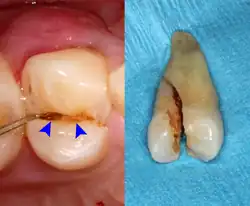

Dental trauma and cracked tooth syndrome

Crown-root fracture with pulp involvement (left). Extracted (right).

Cracked tooth syndrome refers to a highly variable[30] set of pain-sensitivity symptoms that may accompany a tooth fracture, usually sporadic, sharp pain that occurs during biting or with release of biting pressure,[31] or relieved by releasing pressure on the tooth.[10]: 24  The term is falling into disfavor and has given way to the more generalized description of fractures and cracks of the tooth, which allows for the wide variations in signs, symptoms, and prognosis for traumatized teeth. A fracture of a tooth can involve the enamel, dentin, and/or pulp, and can be orientated horizontally or vertically.[10]: 24–25  Fractured or cracked teeth can cause pain via several mechanisms, including dentin hypersensitivity, pulpitis (reversible or irreversible), or periodontal pain. Accordingly, there is no single test or combination of symptoms that accurately diagnose a fracture or crack, although when pain can be stimulated by causing separation of the cusps of the tooth, it's highly suggestive of the disorder.[10]: 27–31  Vertical fractures can be very difficult to identify because the crack can rarely be probed[10]: 27  or seen on radiographs, as the fracture runs in the plane of conventional films (similar to how the split between two adjacent panes of glass is invisible when facing them).[10]: 28–9

The prognosis for a cracked tooth varies with the extent of the fracture. Those cracks that are irritating the pulp but do not extend through the pulp chamber can be amenable to stabilizing dental restorations such as a crown or composite resin. Should the fracture extend though the pulp chamber and into the root, the prognosis of the tooth is hopeless.[10]: 25